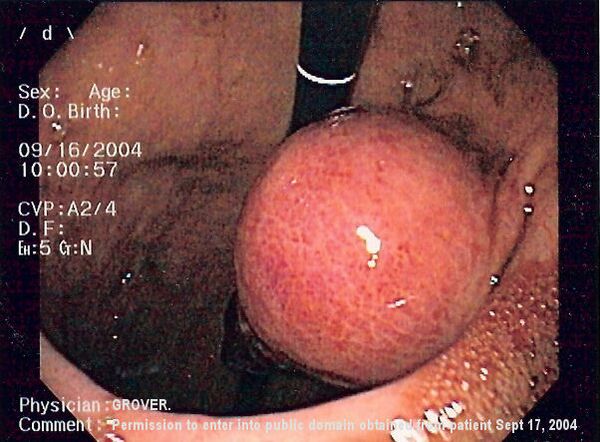

Небольшие ГИСО

Так как ГИСО происходят из мышечного слоя (который располагается глубже слизистого и подслизистого слоёв), небольшие ГИСО чаще визуализируются как подслизистое или внутристеночное объёмное образование. При исследовании желудочно-кишечного тракта с барием обычно выявляются ровные контуры образования, формирующие прямой или тупой угол со стенкой, что наблюдается и при любых других интрамуральных процессах. Поверхность слизистой интактна, за исключением случаев изъязвления, которые присутствуют при 50 % ГИСО. При КТ с контрастным усилением, небольшие ГИСО обычно визуализируются как интрамуральные образования с ровными, чёткими контурами и гомогенным контрастированием.